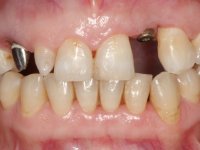

Paciente do sexo feminino, com 47 anos não fumadora. Apresentou-se na consulta com o dente 1.3 com tratamento endodôntico e com um espigão falso coto fundido, reabilitado com uma coroa provisória. Os dois incisivos laterais superiores são conoides e de reduzida dimensão. O dente 2.2 apresenta mobilidade, consentânea com uma significativa reabsorção óssea entre o dente 2.1 e o dente 2.3 Os dois incisivos centrais estão separados por um diastema de 3mm e o dente 2.3 apresenta uma oclusão cruzada com o dente antagonista. Verifica-se também a ausência de alguns dentes posteriores e uma higiene oral razoável. Na segunda intervenção realizada passados 8 anos, verificou-se que os incisivos centrais superiores se apresentavam cromaticamente mais escuros e apresentavam um sulco longitudinal no esmalte que estando pigmentado comprometia esteticamente o sorriso. O trabalho realizado na primeira fase do tratamento mostrava-se competente estética e funcionalmente. Por fim, um ano após a última intervenção, a paciente apresentou-se com uma fratura da faceta colocada no dente 2.1 provavelmente em resultado de estar em contacto com o coto do implante. A rigidez da anquilose implantar, pode ter sido a causa desta fratura. Outros casos deste tipo de fratura já foram observados por mim em situações clínicas idênticas. A faceta do dente 1.2 apresentava-se esteticamente comprometida e a própria estrutura dentária apresentava uma pequena cárie e, pelo que se recomendaria a sua substituição.

• Colocação de um Implante no local do dente 2.2. Reabilitação do implante com um “abutment” de componente coronário e gengival. em que o orifício de acesso ao parafuso fosse “camuflado” com uma faceta feldspática.

O tratamento iniciou-se com a re -preparação do coto do espigão falso coto fundido, com o objetivo de colocar as linhas de acabamento cervical com uma localização intra-sulcular e simultaneamente confecionar uma coroa provisória adaptada. Com um tratamento ortodôntico muito simples, fechou-se o diastema entre os incisivos centrais superiores e estabilizou-se esta posição com um arame colocado na superfície palatina dos centrais, funcionando como contenção. Posteriormente procurou-se fazer uma tração ortodôntica lenta do dente 2.2 com o intuito de diminuir, ainda que muito ligeiramente a perda óssea vertical nessa zona. Finalizada a tração, foi feita a extração do dente 2.2 e a zona foi reabilitada provisoriamente com uma coroa de resina composta colada aos dentes adjacentes. Foi colocado um implante dentário na zona do dente 2.2 sendo novamente colada a coroa provisória em resina, reabilitando provisoriamente a paciente durante o período de osseointegração. No dente 1.3 foi feita uma gengivectomia com bisturi elétrico, com a intenção de subir o nível cervical do 1.3 conseguindo uma maior harmonia com o dente 2.3. Estabilizados os tecidos moles, foi feita uma impressão com a técnica de moldeira aberta, utilizando silicones de adição de consistência “putty” e “light”. A recolha da cor, tanto da componente dentária como dos tecidos moles foi feita pelo ceramista no consultório.  No laboratório as impressões foram passadas a gesso e deram origem a modelos de trabalho que foram devidamente analisados. Foi decidido confecionar um “abutment” metalo-cerâmico aparafusado sobre o implante. Este “abutment” foi fundido com uma liga nobre e posteriormente revestido a cerâmica coronária e gengival. Dada a inclinação do implante o aparafusamento condicionou de forma inevitável a saída do orifício do parafuso pela superfície vestibular. No sentido de esconder esta situação, o desenho do “abutment” já foi idealizado com a intenção de acomodar na superfície vestibular a colagem de uma faceta feldspática. Este “abutment” foi provado em boca e foram feitos ajustes no componente cerâmico gengival. A sua adaptação aos tecidos moles foi feita tanto de forma subtrativa, com broca, como de forma aditiva, acrescentando resina composta de tonalidade gengival. Este acrescento de resina seria orientador do ceramista na colocação final da cerâmica de tonalidade gengival. A coroa que reabilitaria o dente 1.3 foi cimentada nesta consulta de prova com cimento de ionómero de vidro reforçado com resina composta. Finalizado o trabalho em laboratório da faceta sobre o 1.2 e o “abutment” e a faceta para o implante este foi colado em boca, após a colocação do isolamento absoluto. O trabalho satisfez plenamente a paciente. Durante oito anos a paciente foi seguida regularmente, mostrando-se agradada com o tratamento efetuado, no entanto começou a mostrar interesse em intervir esteticamente nos incisivos centrais superiores. Decidida a segunda fase da nossa intervenção, foi feita a preparação dentária dos dentes 1.1 e 2.1 para a colocação de duas facetas feldspáticas. Particular cuidado foi tido na preparação inter-proximal distal junto ao “abutment” do implante. Foi preciso avaliar muito pormenorizadamente o eixo de inserção da faceta em relação ao “abutment”. As facetas feldspáticas foram confecionadas em laboratório e posteriormente coladas em boca após a colocação de isolamento absoluto. Um ano após, iniciamos a nossa terceira fase de tratamento, após a faceta colada no dente 2.1 ter fraturado. A preparação dentária foi feita sobre a faceta colada, procurando estender mais para palatino o interface inter-proximal distal. O objetivo seria passar para mais palatino do ponto de contacto o interface faceta-dente. O preparo dentário do dente 1.2 também foi muito reduzido, limitando-se a criar um eixo de inserção. Após confecionadas a coroa total e a faceta em laboratório foram coladas em boca. Primeiro foi colada a coroa utilizando-se um isolamento relativo com teflon, posteriormente foi colada a faceta após a colocação do isolamento absoluto. Na coroa utilizei este tipo de isolamento para evitar a utilização de grampos. Seria difícil de aplicar pela forma e dimensão do dente e agressivo para os tecidos moles. Após a colagem foi avaliada a integração oclusal do trabalho.